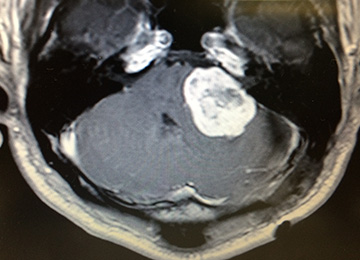

右小脳橋角部(右耳の奥)の腫瘍

脳を腫瘍が圧迫している